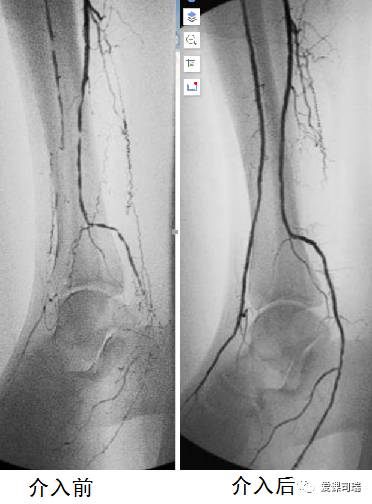

介入血管造影,血管狭窄闭塞及治疗后改善情况一目了然